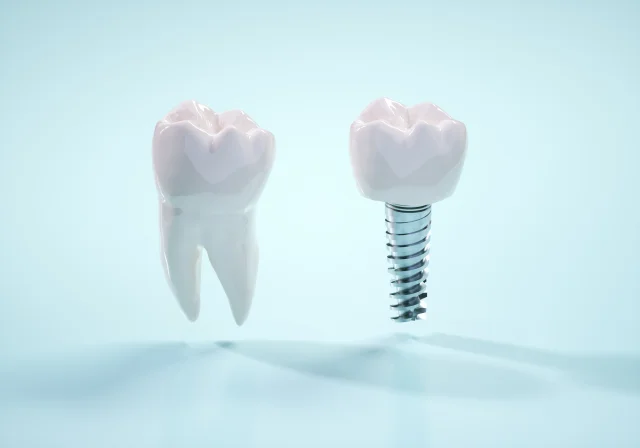

審美歯科

保険が適用される虫歯や歯周病の治療などを提供しています。

保険治療であるからといって手を抜くようなことは一切ございません。

当院では、患者さんの健康と安全を最優先に考え、最新の診療技術と高品質な材料を使用して治療を行っております。

一般歯科治療では、以下のような症状や問題に対応しています。

- 虫歯や歯の表面の損傷による詰め物の治療

- 歯茎の炎症や歯周病の治療

- 歯の抜歯や親知らずの抜歯

- 噛み合わせの異常や歯の欠損による修復治療(クラウンやブリッジなど)

当院では、患者さんの個別の状況に合わせて、丁寧なカウンセリングと診断を行い、最適な治療プランを提案いたします。

保険治療の範囲内で、最善の治療をご提供することをお約束いたします。

ぜひ、当院で健康で美しい笑顔を保つお手伝いをさせてください。

お気軽にご相談ください。